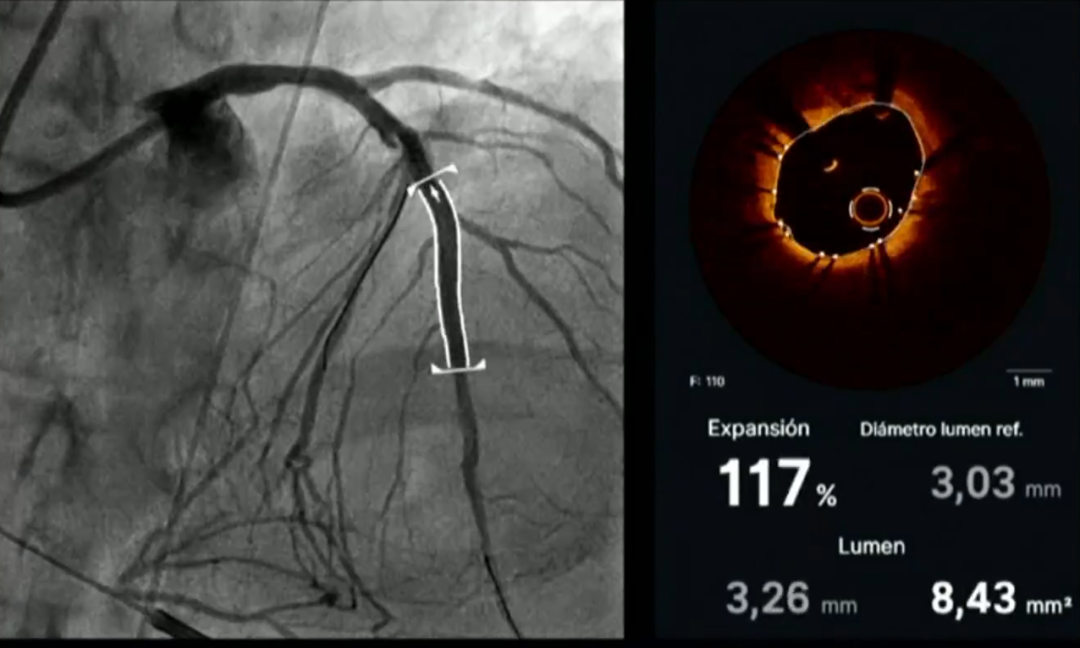

她介绍道,治疗前OCT显示左前降支钙化狭窄部位的血管管腔大多数在0.90mm以下,IVL治疗后OCT显示钙化斑块出现多角度的钙化断裂带,多处管腔直径达到了1mm以上,支架置入后管腔得到进一步充分扩张,平均管腔面积达到6.00mm²(如图7),支架膨胀非常完全,达到117%

图片

图7